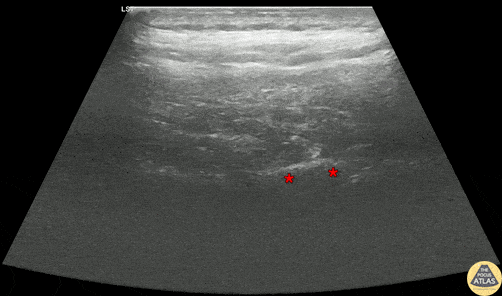

30s M PMH ETOH pancreatitis presented with epigastric and upper abdominal pain in the setting of running out of his analgesic medications. To aid in pain control, an erector spinae plane block was performed. The block is shown here, with the needle entering from the cranial aspect to the thoracic process (*). Anesthetic was injected and observed to spread in the plane between the transverse process and the overlying erector spinae muscles. The patient had significant improvement in his pain and was able to be discharged with outpatient folllow up. Dr. Nhu-Nguyen Le, Fellow Denver Health Ultrasound Fellowship